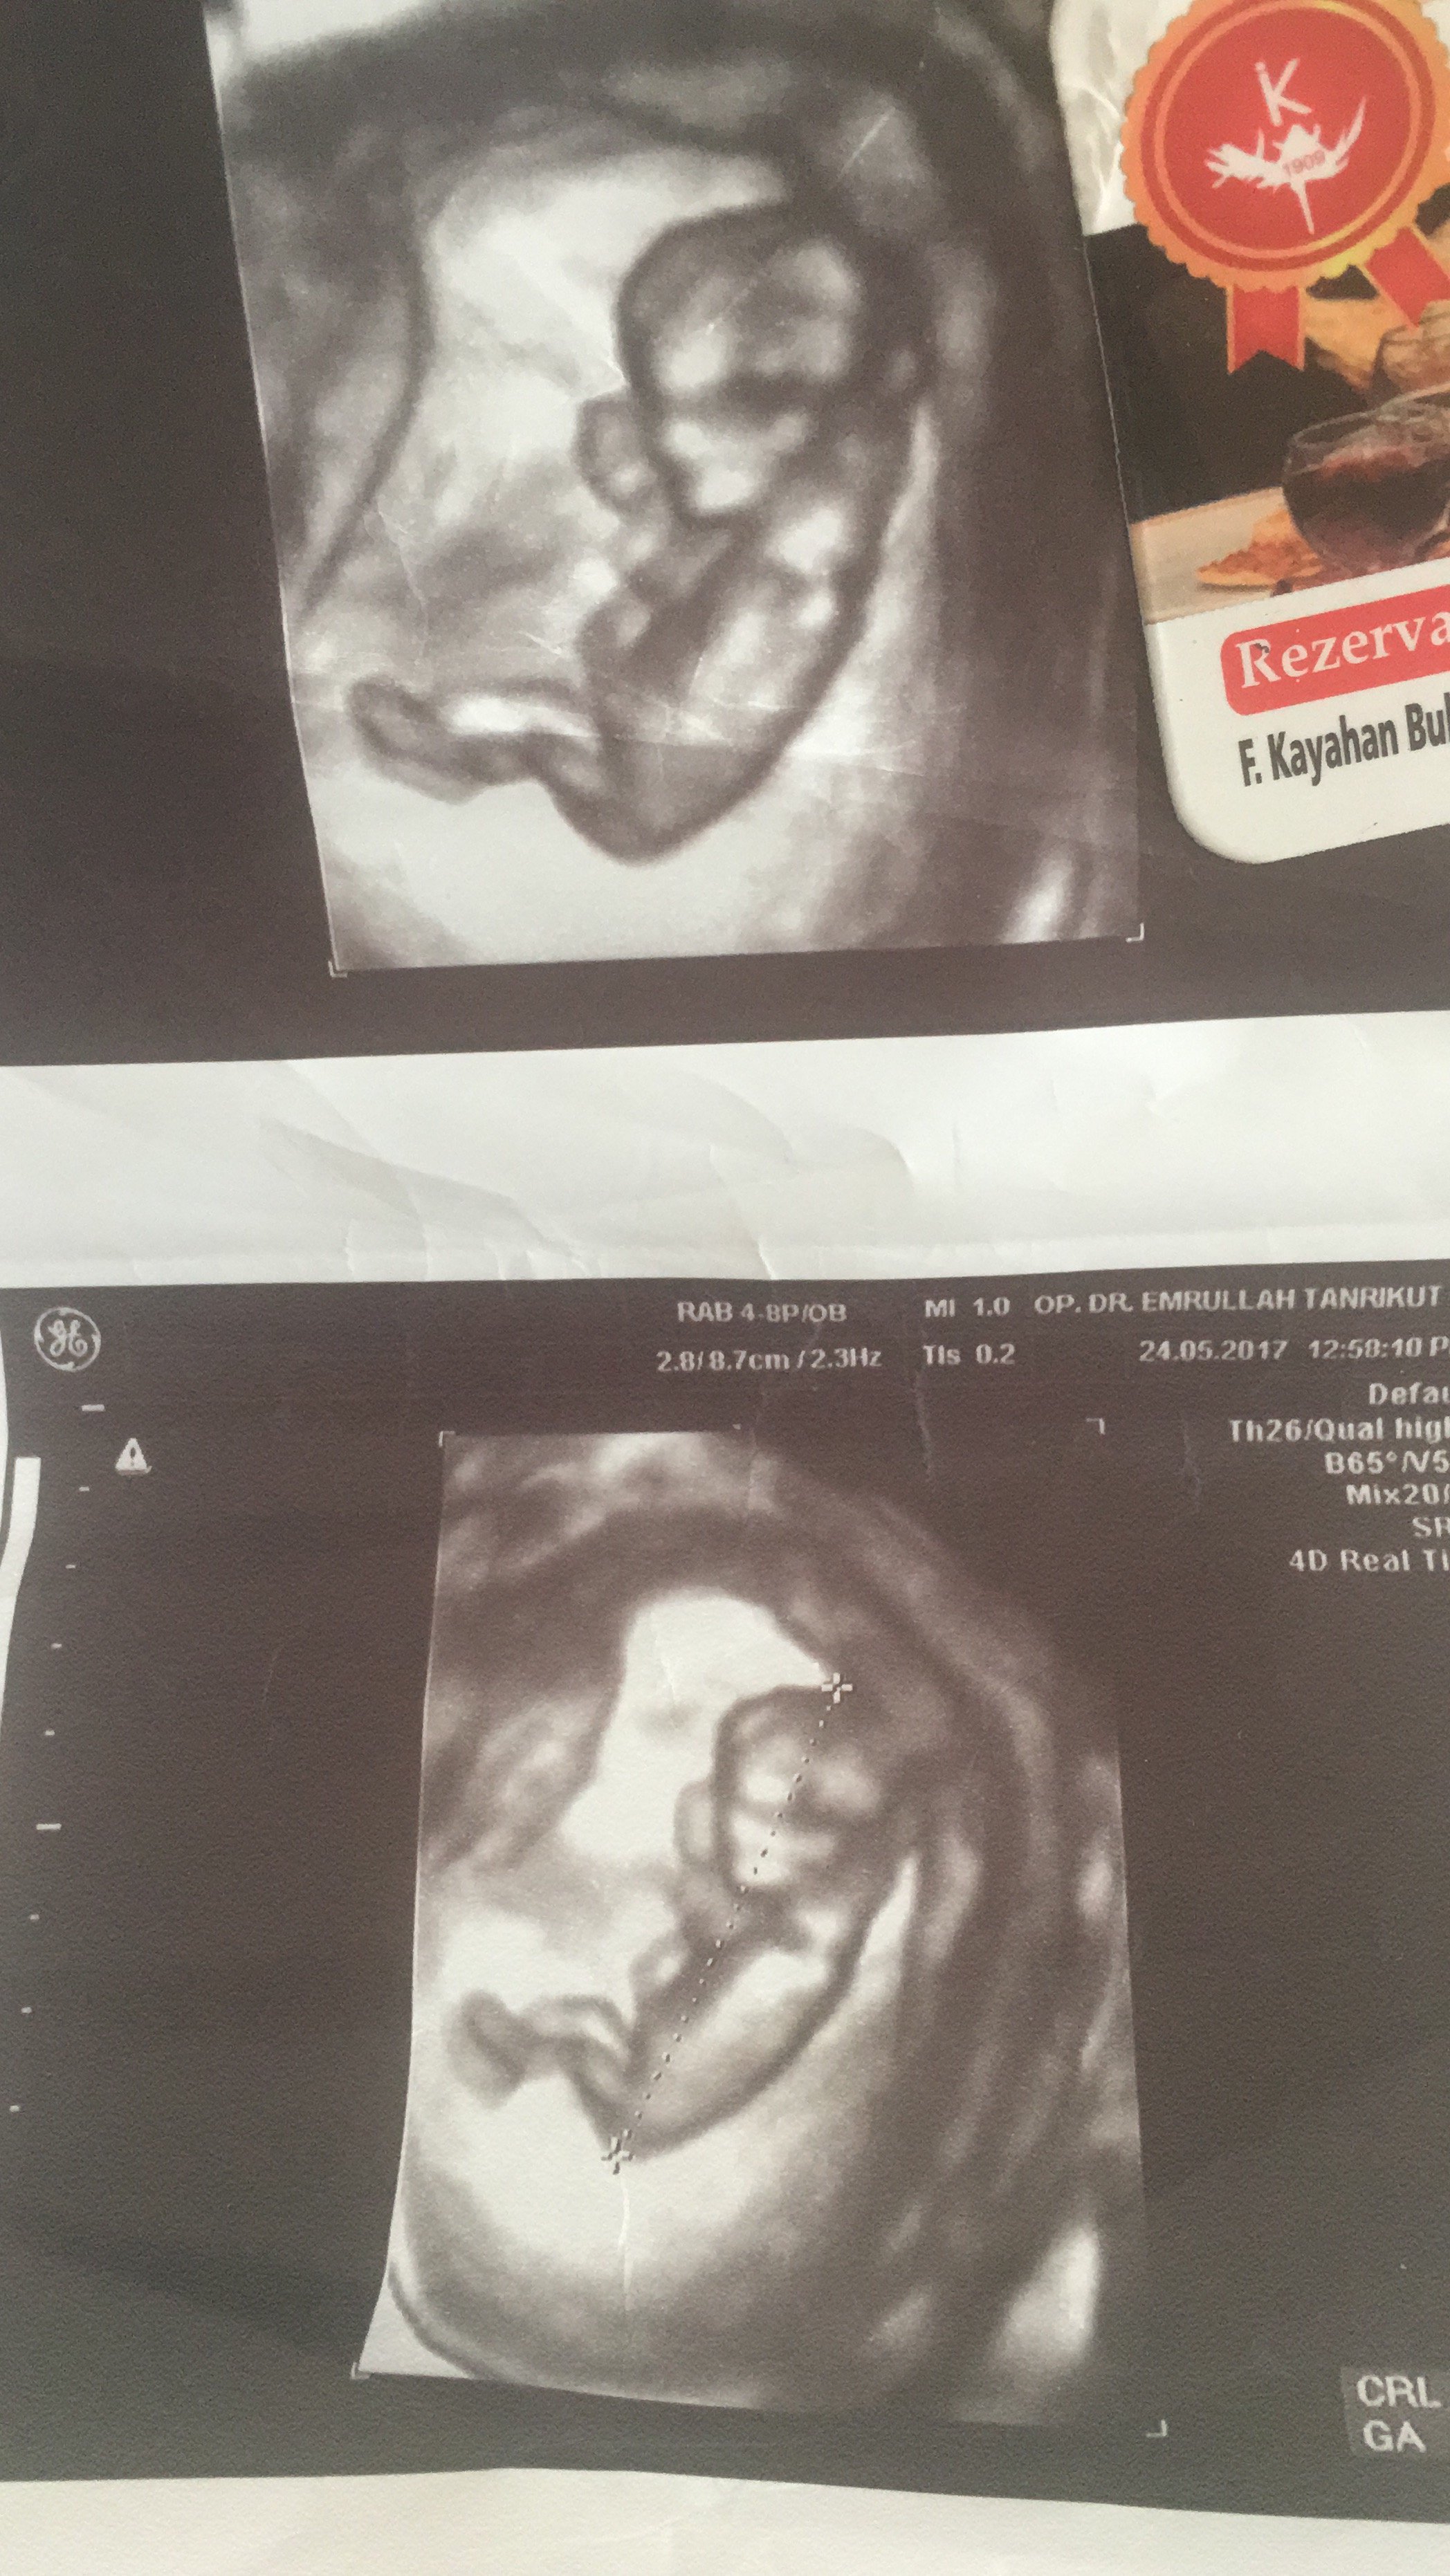

M Mina09 Yeni Üye Üye 31 Mayıs 2017 #293 Merhaba hanımlar benim meleğim de 12 haftalık cinsiyetini merak ediyorum sağlıklı olması herşeyden önemli tabi ama tahmin yapabilecek olan var mı?

Merhaba hanımlar benim meleğim de 12 haftalık cinsiyetini merak ediyorum sağlıklı olması herşeyden önemli tabi ama tahmin yapabilecek olan var mı?

Uzman SühaN Administrator 31 Mayıs 2017 #294 Merhaba resim çok küçük ve nub çıkıntısı anlaşılmıyor. Bu yüzden değerlendirme yapamıyoruz..